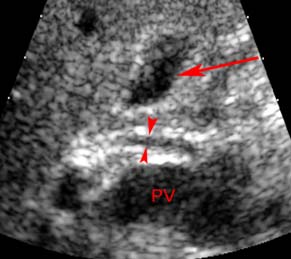

Các nhà nghiên cứu Lim JH, Mairiang E, Ahn GH đang công tác tại khoa chẩn đoán hình ảnh, Trung tâm nghiên cứu y học Samsung Medical Center, đại học y khoa Sungkyunkwan, Seoul, Hàn Quốc, đã tiến hành một nghiên cứu tổng thể về các bệnh ở đường mật do ký sinh trùng: sán lá gan lớn và sán lá gan nhỏ (Clonorchis sinensis, Opisthorchis viverrini). Các sán này nằm trong các đường mật nhỏ ngoại vi của gan và có thể dẫn đến hâuu quả viêm nhiễm mạn tính, dãn đường mật, tắc nghẽn cơ học đường mật và dày thành ống mật. Về hình ảnh học, các đường mật ngoại vi nhỏ bị dãn nhưng các đường mật lớn và ngoài gan không dãn hoặc dãn rất nhẹ. Không thấy tắc nghẽn đường mật. Đôi khi, nhiễm trùng nặng, các sán trưởng thành có thể thấy được qua siêu âm, CT hoặc MRI đường mật và hệ gan mật và có thể thấy các tổn thương nhỏ trong gan mật đi kèm. Những con sán trong túi mật có thể trôi nổi trong túi mật, các vật thể nhỏ này thấy qua siêu âm. Nhiễm mạn tính có thể dẫn đến bệnh lý ung thư biểu mô đường mật trong nhu mô gan và đường mật. Nhiễm sán lá gan lớn ở người loại Fasciola hepatica, có thể xảy ra tình cờ, sán di chuyển trong nhu mô gan (pha cấp) hoặc pha mạn trong đường mật. Chẩn đoán hình ảnh trong pha gan là các hình ảnh ổ áp xe li ti, đa ổ và hoại tử lớn nhỏ khác nhau, dạng đường hầm hoặc khoang, chứng minh có ký sinh trùng di chuyển trong nhu mô gan. Trong pha đường mật (mạn tính), sán có thể nằm trong đường mật trong và ngoài gan hoặc túi mật, dưới dạng các vật thể trôi nổi và dãn đường kính.